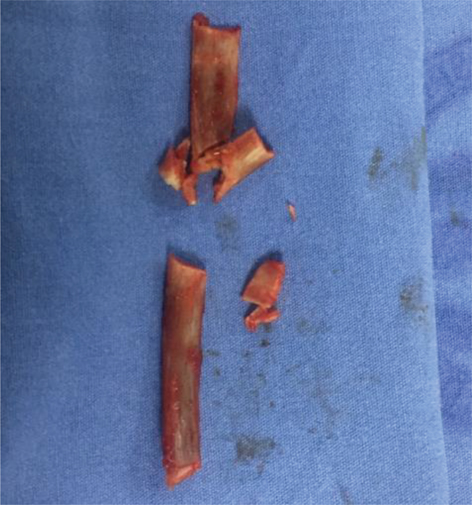

In order to proceed with the rib removal, a notch with gouge was made (Fig. 3). The anterior segment was taken by the side edge, slightly tracing and removing the periosteum remnants with a chisel, until the cartilage was visualized, and finally, a new notch was made to cut the rib. These same steps were followed to remove the anterior segment. Throughout the procedure, excessive use of cautery was avoided (Figs. 47).

Fig 3

Fig. 3. The distraction with gouge generates to segments, posterior, and anterior.

Fig 4

Fig. 4. Rib removal.

Fig 5

Fig. 5. Rib removal.

Fig 6

Fig. 6. Rib removal.

Fig 7

Fig. 7. The 11th rib.